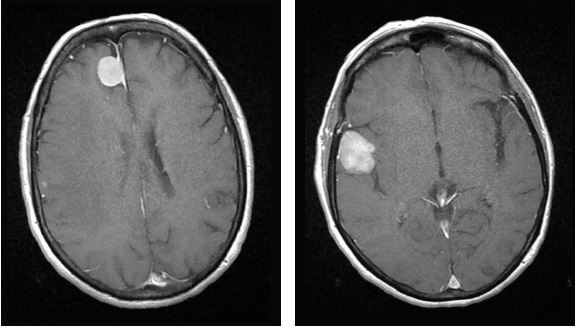

На Т1: Обидва ураження виглядають ізоінтенсивними по відношенню до сірої речовини (СМ) на Т1-зважених зображеннях

Т1 гадоліній: Обидва ураження демонструють інтенсивне та гомогенне контрастне підсилення на Т1-зображеннях. Парафалькоріальне ураження, схоже, пов'язане з мозолистим тілом через дуральний хвіст, що вказує на екстрааксіальне ураження.

Кортикотерапія призвела до значного зменшення лімфоми та перилімфоїдного набряку.